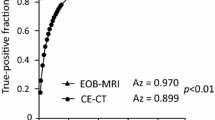

MRI detected 489 liver metastases and MDCT 384. In terms of per-lesion sensitivity in the detection of liver metastasis, all three readers had higher diagnostic sensitivity with Gd-EOB MRI than with MDCT (95.5% vs. 72% reader 1; 90% vs. 72% reader 2; 96% vs. 75% reader 3). Each reader showed a statistical significant difference (p < <.001 at Chi square test). MR imaging showed a higher performance than MDCT in per-patient detection sensitivity (100% vs. 74.2% [p < <.001] reader 1, 98% vs. 73% [p < <.001] reader 2, and 100% vs. 78% [p < <.001] reader 3). In the control group, MRI and MDCT showed similar per-patient specificity (100% vs. 98% [p = 0.31] reader 1, 100% vs. 100% [p = 0.92] reader 2, and 100% vs. 96% [p = 0.047] reader 3). Inter-reader agreement of lesion detection between the three radiologists was moderate to excellent (k range, 0.56–0.86) for Gd-EOB MRI and substantial to excellent for MDCT (k range, 0.75–0.8).

The median interval between MDCT and pathologic confirmation was 15 days. The median interval between MRI and pathologic confirmation was 7 days. We analyzed 512 liver metastases in 128 CRC patients. Lesions size ranged from 12 to 58 mm (median, 28 mm). In terms of per-lesion sensitivity in the detection of metastases, all three readers had higher diagnostic sensitivity with Gd-EOB MRI than with MDCT (95.5% [489 of 512] vs. 72.3% [370 of 512] for reader 1; 89.8% [489 of 512] vs. 71.8% [368 of 512] for reader 2; 96.3% [493 of 512] vs. 75% [384 of 512] for reader 3). Each reader showed a statistical significant difference (p < <.001 at chi square test (Table 3). By consensus of three readers, the MRI detected 489 liver metastases while MDCT 384 liver metastases.

MRI showed higher performance than MDCT in per-patient detection sensitivity, (100% [128 of 128] vs. 74.2% [95 of 128] [p < < .001] for reader 1, 97.7% [125 of 128] vs. 72.6% [93 of 128] [p < < .001] for reader 2, and 100% [128 of 128] vs. 78.1% [100 of 128] [p < < .001] for reader 3), with a statistical significant difference (Table 3).

In the control group, MRI and MDCT showed similar per-patient specificity (100% [46 of 46] vs. 97.8% [45 of 46] [p = .31] for reader 1, 100% [46 of 46] vs. 100% [46 of 46] [p = .92] for reader 2, and 100% [46 of 46] vs. 95.6% [44 of 46] [p = .047] for reader 3) (Table 3).

Inter-reader agreement of lesion detection between the three radiologists was moderate to excellent (k range, 0.56–0.86) for Gd-EOB MRI and was substantial to excellent for MDCT (k range, 0.75–0.8).